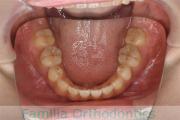

No.23V-478

- 主な症状:

- 叢生

- 年齢:

- 30歳

- 性別:

- 男性

- 抜歯部位

- 上:

- 44済

- 下:

- 8558済

- 主な使用装置:

- FEA 022

- 治療にかかった費用:

- 76万円

右上の歯が重なっているところが邪魔になるとのことで矯正治療を始められた患者さんで、札幌から転院されました。当院で約1年半、15回程度の通院が必要でした。叢生(でこぼこ、凹凸、ガタガタ)が強く、後戻りのリスクが高いケースです。